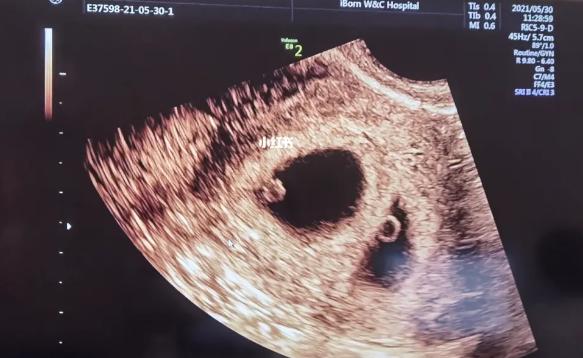

我们需要明确一点,胎心和胎芽是两个不同的概念。所谓的“100天才有胎心”,通常指的是在怀孕约6周左右,也就是距离末次月经约45天时,通过B超检查还无法发现任何形态的怀孕卵,但此时如果再等待1-2周进行B超检查,则可以看到大约3毫米左右大小、类似豆子形状的小团块,这就是所谓的“胚芽”。而当这个小团块发育到7-8周时,就会出现一颗小小的、跳动着的心脏,这就是“胎心”。

很多人认为只有在怀孕100天后才能听到宝宝的心跳声。实际上在医院里通过专业设备检测往往可以在怀孕6周左右就听到并观察到宝宝的心跳情况。而当宝宝发育到10周左右时,则可以用普通听诊器听到清晰而明显的胎心声。